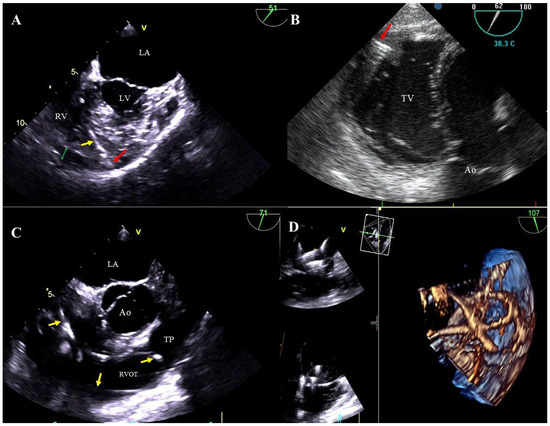

Figure 2. TEE images (2D, 3D) showing vegetations on CIED leads. Various-shaped structures representing bacterial vegetations (blue circles) are visualized on the leads (yellow arrow) in the right atrium. D TEE (A,C), 3D TEE (B,D).

Bacterial vegetations: multi-shaped, irregular, of varying size, balloting formations of heterogeneous echogenicity. Vegetations are diagnosed if there are signs of a generalized infection (positive inflammation markers, blood cultures) or local infection (generator pocket infection) (Figure 2A–D, Movie S4).